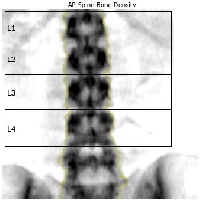

Kręgosłup |

DENSYTOMETRIA KRĘGOSŁUPA LĘDŹWIOWEGO Standardowo zaleca się wykonywanie takich oznaczeń co 12 miesięcy, na tym samym aparacie , w tej samej lokalizacji oraz najlepiej przy tej samej osobie obsługującej urządzenie (najmniejszy błąd pomiarowy).

Wg zaleceń Międzynarodowego Stowarzyszenia Densytometrii Klinicznej (ang. International Society for Clinical Densytometry) z roku 2007 pomiar gęstości mineralnej kości (ang. BMD – Bone Mineral Density) kręgosłupa lędźwiowego L1 – L4 jest zalecany do łącznej oceny z wynikami morfometrycznym metodą DXA (VFA ang. Vertebral Fracture Assessment) oraz oceną klinicznych czynników ryzyka złamań. |

Obecnie uznaje się, że podstawowym i preferowanym miejscem oceny densytometrycznej powinno być badanie nasady bliższej kości udowej, głównie z oceną szyjki kości udowej oraz oceną części lędźwiowej kręgosłupa w obrębie kręgów L1-L4.

Podczas badania przeprowadzanego w pozycji leżącej na plecach zostaje wykonany pomiar gęstości mineralnej kości (ang. BMD – Bone Mineral Density) kręgosłupa lędźwiowego L1 – L4. W przypadku pomiarów kolejnych aparat LUNAR PRODIGY ADVANCE z oprogramowaniem enCORE porównuje procentowo wyniki z poprzednimi oznaczeniami i umiejscawia je na wydruku, który otrzymuje pacjent.

Badanie zostaje wykonane przy niskich względem klasycznej metody RTG dawkach promieniowania jonizującego. Jest więc bezpieczniejsze i mniej szkodliwe oraz istnieje możliwości ponownego badania w krótkim czasie. Poza tym zastosowanie najnowszych rozwiązań technologicznych gwarantuje wysoką jakość obrazu oraz standaryzowaną procedurę pomiaru.